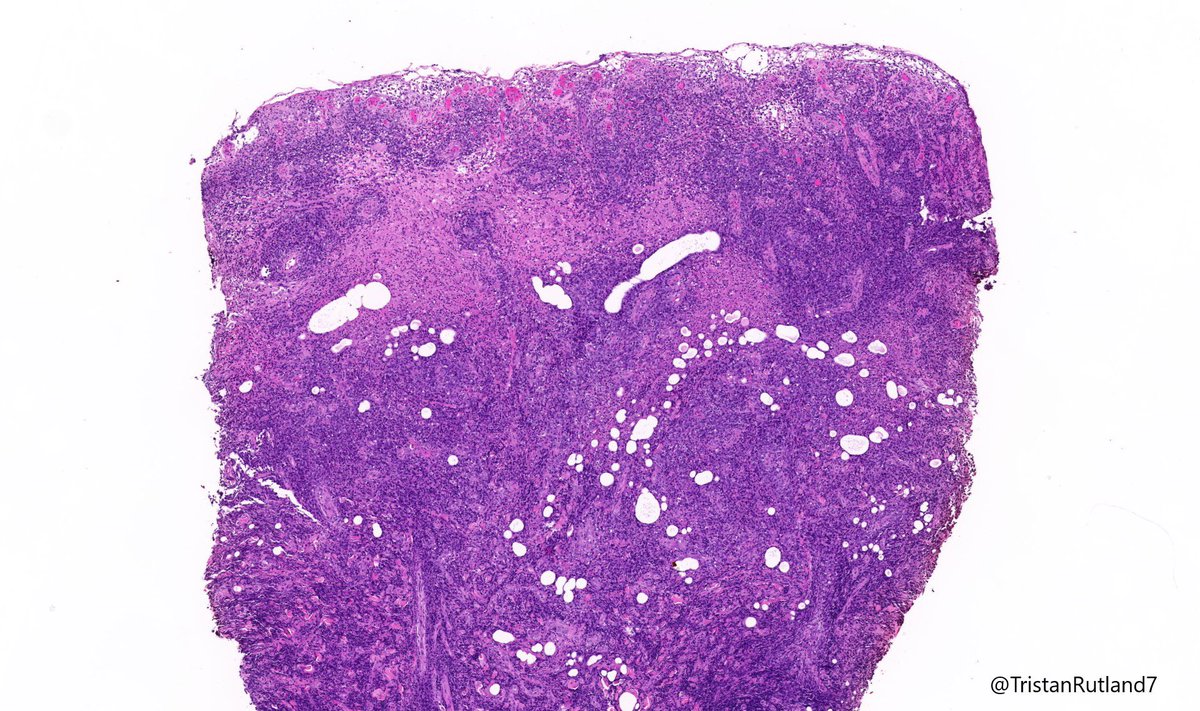

Female, adult, leg.

Large cell transformation of mycosis fungoides (MF).

3/ Large cell transformation is defined by greater than 25% large cells (4X size normal lymphocytes) or nodular aggregates in dermis.

4/ It usually arises from tumour stage (rare cases arising from patch stage have occurred).